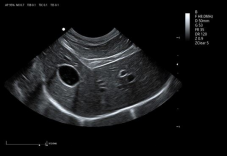

6C1PDA ● 2.5-13.5MHz ● Micro convex array probe ● For Abdomen, Cardiology, Reproduction |

3C5PDS ● 1.0-7.5MHz ● Convex array probe ● For Abdomen and Reproduction |

10L2PD ● 4.2-16.0MHz ● High-frequency linear array probe ● For Abdomen and Small Parts |

8L4PF ● 4.2-16.0MHz ● High-frequency linear array probe ● For Abdomen and Small Parts |

7L4PD ● 4.2-15.0MHz ● Linear array probe ● For Abdomen and Small Parts |